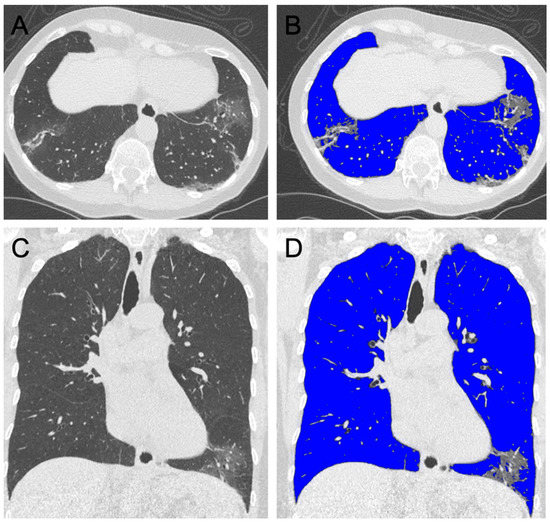

2.4. Semi-Automated Lung Parenchyma Volume Quantification